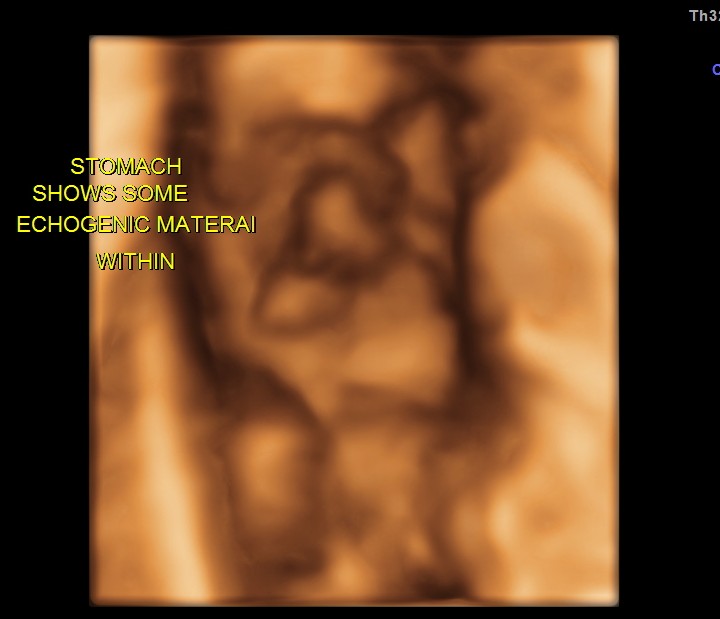

Echogenic material is seen within the stomach.

The following are 3 d images , which prove that this was not an artefact.

At US examination from the second trimester onward, the fetal stomach appears as a uniformly anechoic, sharply circumscribed round structure in the left upper quadrant. However, debris is commonly visualized in the stomach, forming a pseudomass.

The origin of echogenic masses within the gastric lumen is incompletely understood. As they are seen in multiple planes, technical issues are unlikely. They may be due to swallowed cells that aggregate because of the relatively poor peristaltic activity in the stomach early in the second trimester . When intraamniotic bleeding has occurred, these pseudomasses are commonly visualized. They inevitably disappear during follow-up examinations and are not associated with an adverse neonatal outcome. Therefore, further evaluation of this finding is not required.